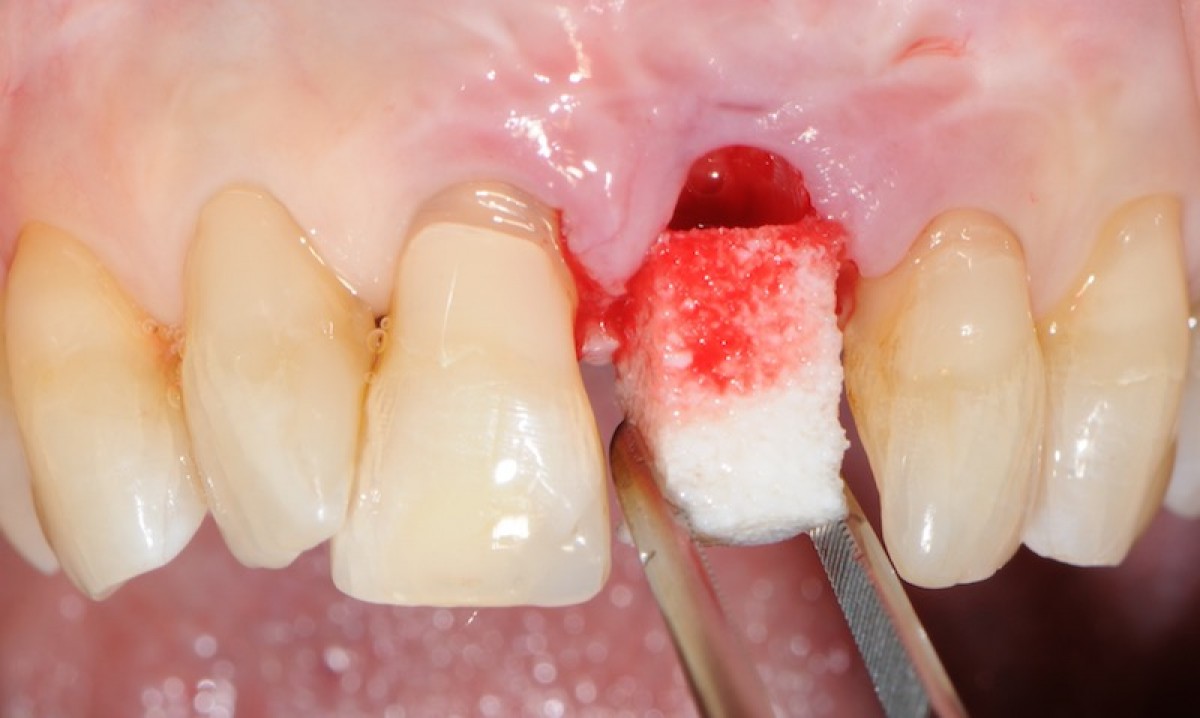

The objective of this prospective cohort study is to test the performance of a new xenogenic collagen matrix as a socket sealing material, to allow second-intention healing of post-extractive sockets filled with a xenogenic bone substitute or with an immediate submerged implant.

10 patients were recruited, presenting a single-rooted tooth scheduled for extraction. After atraumatic tooth removal, the post-extractive alveolus received either a socket preservation procedure or an immediate submerged implant. In both cases, the gingival margins of the alveolus were sealed with a xenogenic collagen matrix (Mucoderm, Botiss Dental, Zossen, Germany). The following parameters were evaluated:

• the mean post-operative exposure area of the matrix was 26.25 mm2 (14.2 to 38.84 mm2 );

• 8 weeks after surgery, full wound closure was achieved in 9 out of 10 sites with healthy keratinized tissue;

• the mean colorimetric score ∆E between the regenerated site and the surrounding gingiva was 3.76 (3 to 6.55).

Seven out of 10 patients reported an excellent aesthetic integration of the matrix (∆E < 3.7).